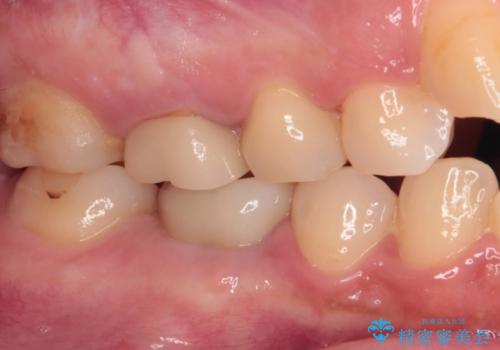

初診から2年以上が経過していますが、排膿路が再発することはなく、良好な状態を保っています。